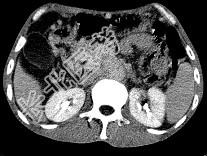

单项选择题女,50岁, 中上腹疼痛,消瘦乏力, 影像检查如下图,最佳的诊断为( )

A、胰岛素瘤

B、慢性胰腺炎

C、急性胰腺炎

D、腹膜后淋巴瘤

E、胰腺癌并腹膜后淋巴结转移